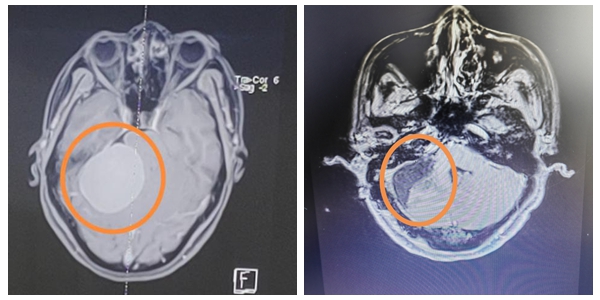

听闻湘雅常德医院有袁贤瑞教授坐诊,朱阿姨在家人的陪同下来到湘雅常德医院神经外科寻求帮助。入院后,头颅CT结果提示:右侧桥小脑角区占位,脑膜瘤可能。肿瘤巨大,约6*5cm大小,需要尽快手术治疗。

严格缜密的术前评估和手术方案制定好后,袁贤瑞教授凭借精湛的手术技巧和丰富的临床经验,在尽可能保护脑组织的情况下,“精雕细琢”对肿瘤精细剥离,最终将这个约5.5cmx5cmx4.8cm的巨大脑膜瘤全部切除且周围神经血管保护完好。手术圆满成功!